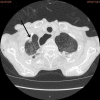

The author herein reports a large cell neuroendocrine carcinoma (LCNEC) of the lung diagnosed at a brain metastasis without clinical data. A 70-year-old man underwent esophagectomy for esophageal squamous cell carcinoma, and was treated with chemotherapy. At 72 years of age, he was found to have prostatic well differentiated adenocarcinoma, and treated by estrogen. At 78 years of age, he was pointed out to have gastric advanced tumor, and the biopsy showed moderately differentiated tubular adenocarcinoma. The gastric carcinoma was treated by chemotherapy. At 79 years of age, he was shown to have right lung shadow (2 cm in diameter) and brain shadow (cerebellar vermis) of 1 cm in diameter. Multiple biopsy and cytology of the lung failed to detect carcinoma cells. Biopsy of the brain was performed. The biopsy showed medullary undifferentiated carcinoma. Immunohistochemically, the tumor cells were positive for pancytokeratin AE1/3, synaptophysin, CD56 (NCAM), p53, Ki67 (labeling 40%), KIT and TTF-1, but were negative for vimentin, chromogranin, neuron-specific enolase and PDGFRA. A pathological diagnosis of metastatic LCNEC form the lung was made. A molecular genetic analysis for KIT (exons 9, 11, 13, and 17) and PDGFRA (exons 12 and 18) genes identified no mutations of the KIT and PDGFRA genes. The patients died of carcinomatosis one month after the diagnosis. In conclusion, careful histological and immunohistochemical examination can diagnose LCNEC of the lung at the metastatic site.